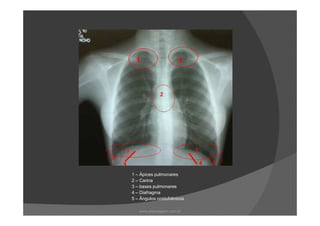

As regiões radiograficamente importantes do

pulmão são:

Ápice

Carina

Base

DiafragmaDiafragma

Ângulo costofrênico

Tórax PA

1 – Ápices pulmonares

www.playmagem.com.br

2 - Carina

2 – Carina

3 – Bases pulmonares

4 – Diafragma

5 – Ângulos costofrênicos